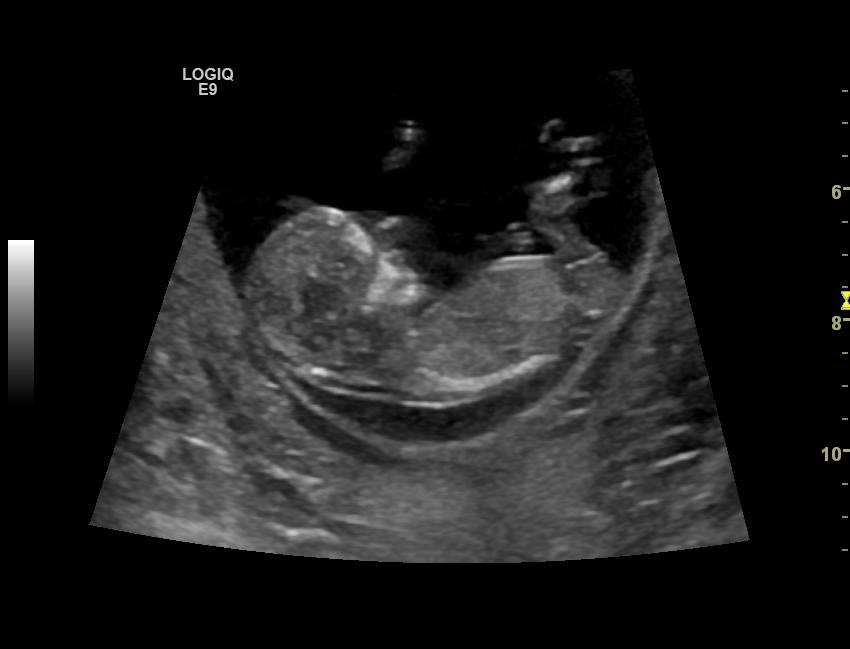

Boy or girl based in nub or skull theory?!Attachment 16304

Leaning girl, congrats! x

Looks pretty pink in angle. A little bulbous, but ill still lean pink. What was the gestation this was taken at?

12 weeks 2 days